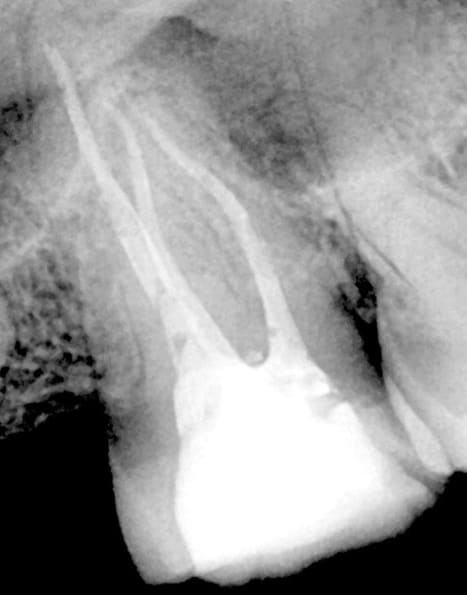

A 55-year-old patient presented for endodontic therapy with a diagnosis of irreversible pulpitis affecting a maxillary premolar. Radiographic assessment revealed partially calcified canal trajectories, suggesting chronic pulp inflammation (Figure 2). After conventional access and irrigation with Dual Rinse® (1.5% sodium hypochlorite [NaOCl] combined with a chelating agent compatible with NaOCl) (Medcem GmbH, medcem.eu), an EdgeOne Blaze Utopia R20 file was selected for canal preparation.